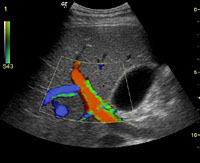

腹部エコー(肝門脈)